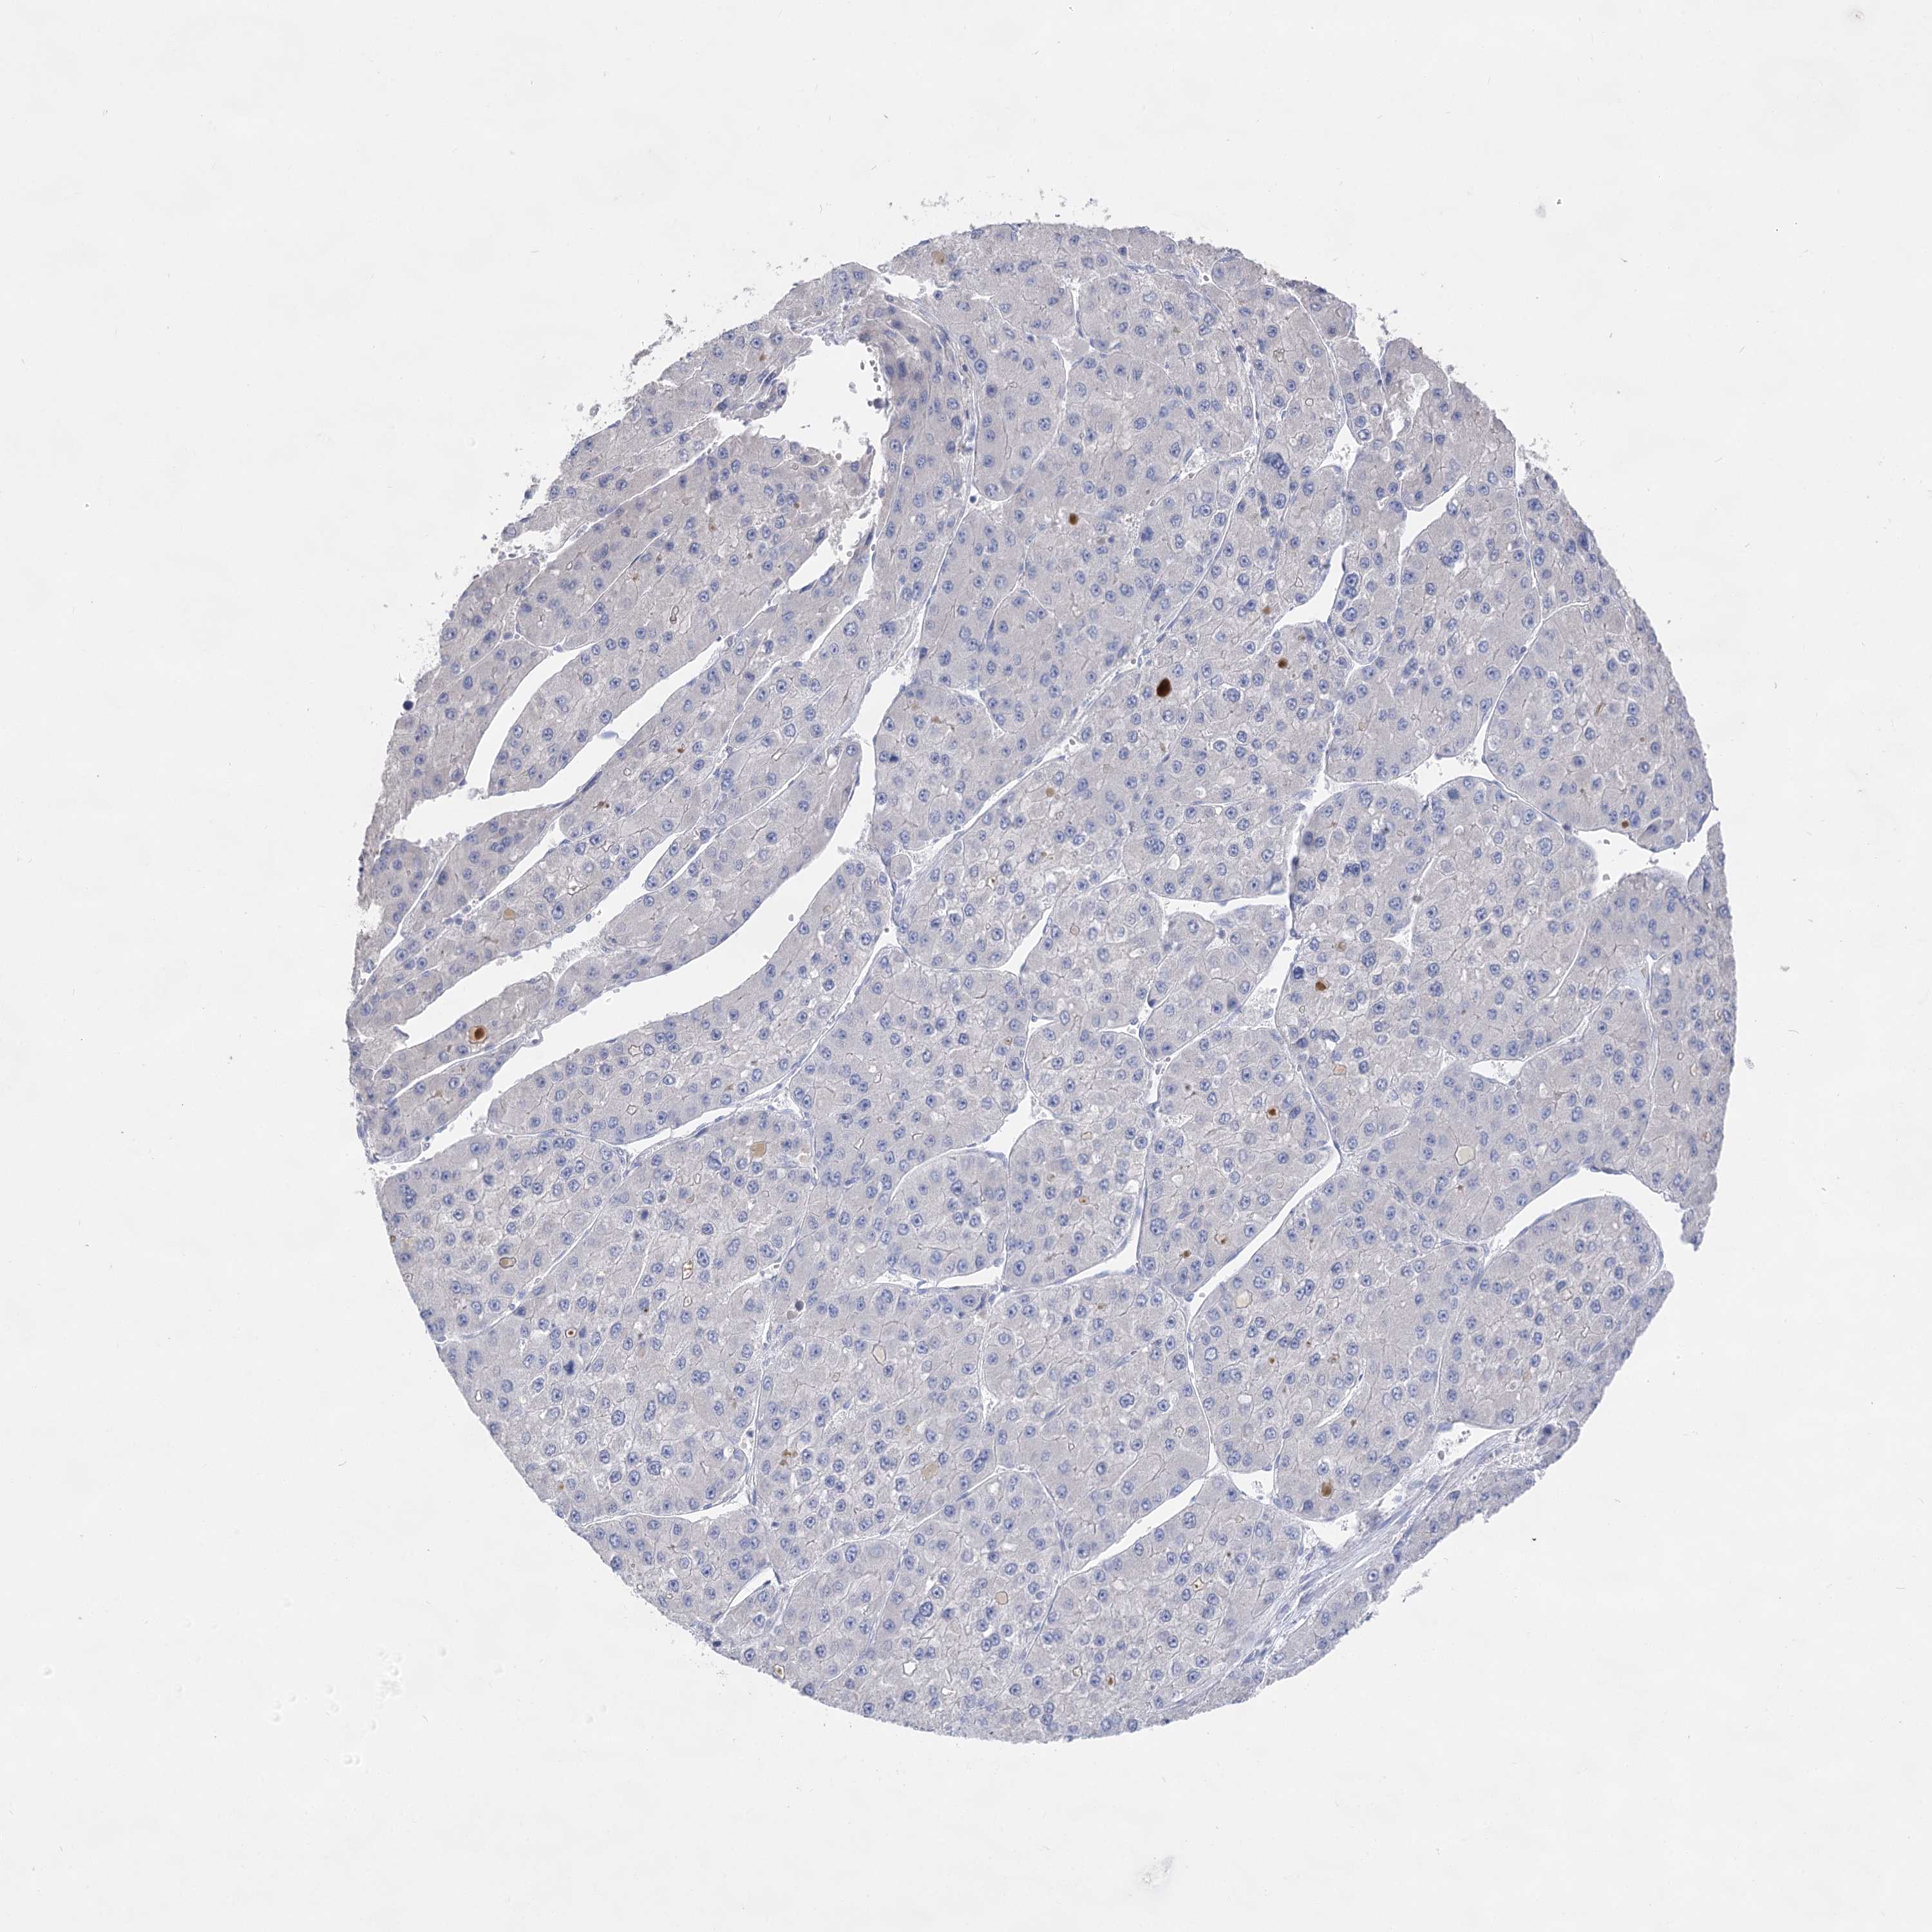

LIVER CANCER - Protein expressioni

A mouse-over function shows sample information and annotation data. Click on an image to view it in a full screen mode. Samples can be filtered based on level of antibody staining by selecting one or several of the following categories: high, medium, low and not detected. The assay and annotation is described here.

Note that samples used for immunohistochemistry by the Human Protein Atlas do not correspond to samples in the TCGA dataset.

Antibody stainingi

Antibody staining in the annotated cell types in the current human tissue is reported as not detected, low, medium, or high, based on conventional immunohistochemistry profiling in selected tissues. This score is based on the combination of the staining intensity and fraction of stained cells.

Each image is clickable and will lead to virtual microscopy that enables deeper exploration of all samples and also displays staining intensity scores, fraction scores and subcellular localization as well as patient and tissue information for each sample.

Antibody HPA037953

Antibody HPA037954

Staining

High

Medium

Low

Not detected

Intensity

Strong

Moderate

Weak

Negative

Quantity

>75%

75%-25%

<25%

None

Location

Nuclear

Cytoplasmic/membranous

Cytoplasmic/membranous,nuclear

Cholangiocarcinoma

Carcinoma, Hepatocellular, NOS